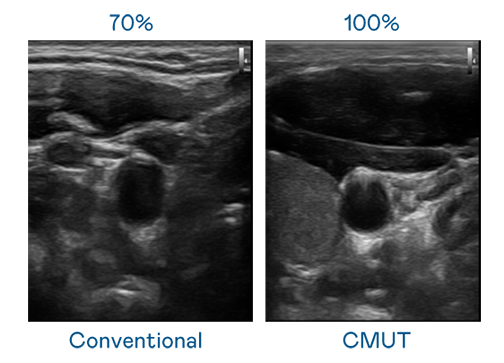

CMUT 技术是一种用电容式微机电元件来产生超音波讯号的技术。与传统 PZT 压电式技术相比,CMUT 频宽增加 30%,更宽频的超音波讯号让影像解析度大幅提升,是实现高影像品质医疗超音波扫描、促进精准医疗发展的关键技术。

大频宽带来超清晰影像

超音波影像的解析度高低,首先取决于探头能发出的讯号频宽。优游ub8国际 CMUT 可提供高清晰的超音波讯号,提供高频宽、高灵敏度、影像纹理细节更高的超音波影像,协助医护人员缩短影像判读时间及利用精准的医疗影像进行诊断。